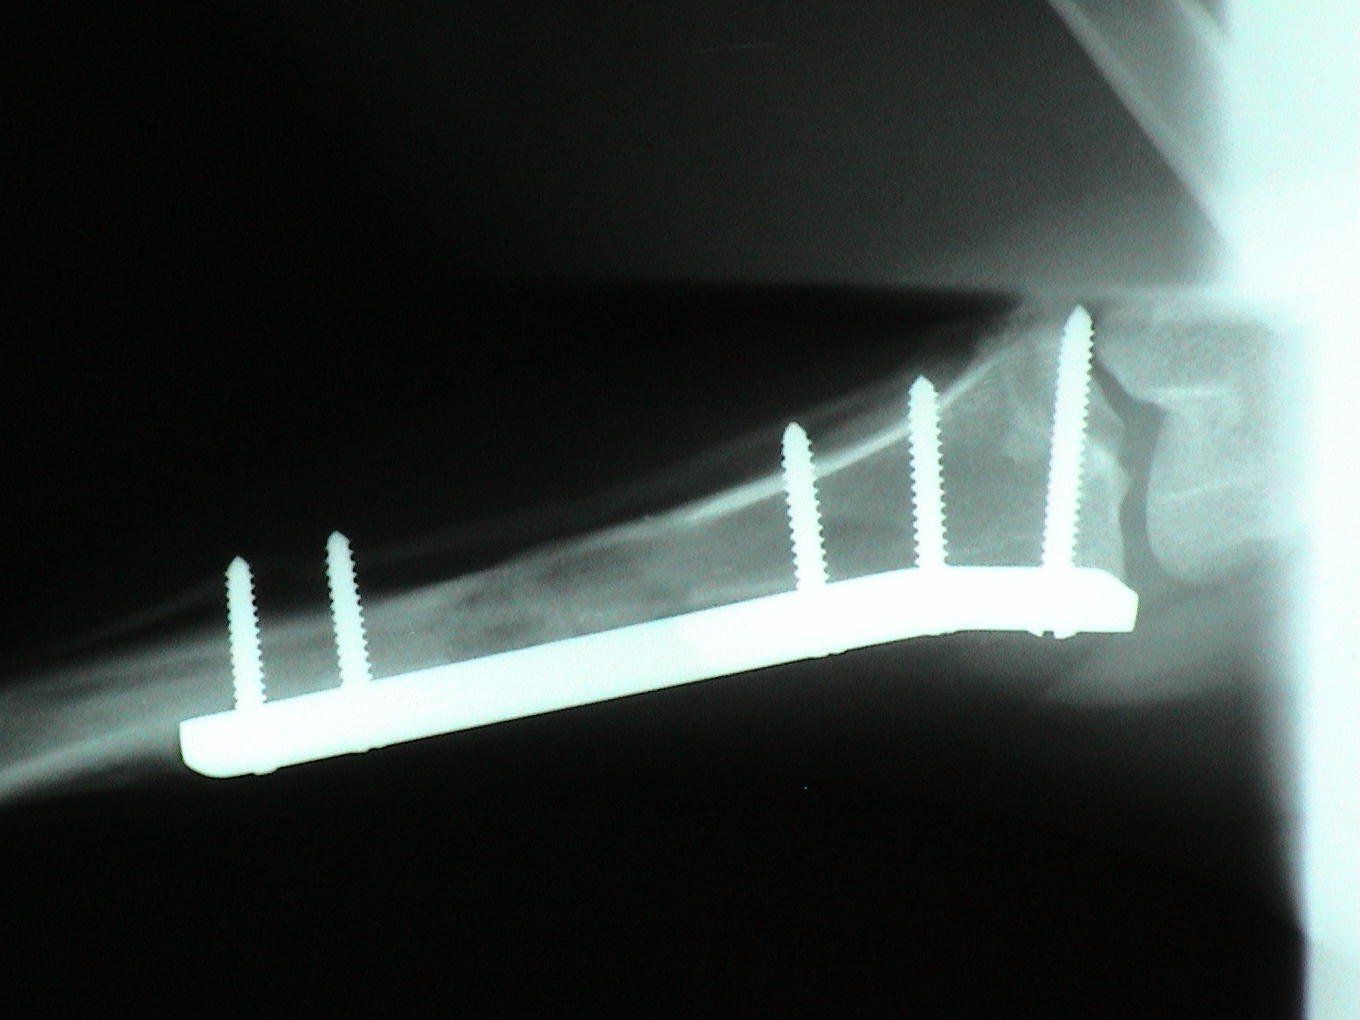

Dogs and cats commonly experience fractures secondary to trauma. The most common cause of the trauma is being hit by a car. Other trauma such as falls from furniture, jumping on unstable surfaces, leaping from a person's arms, etc. can also result in fractures. Below are some x-rays of some of the fractures we have seen at All Pets and their surgical correction using pins, plates, screws, and/or wires.